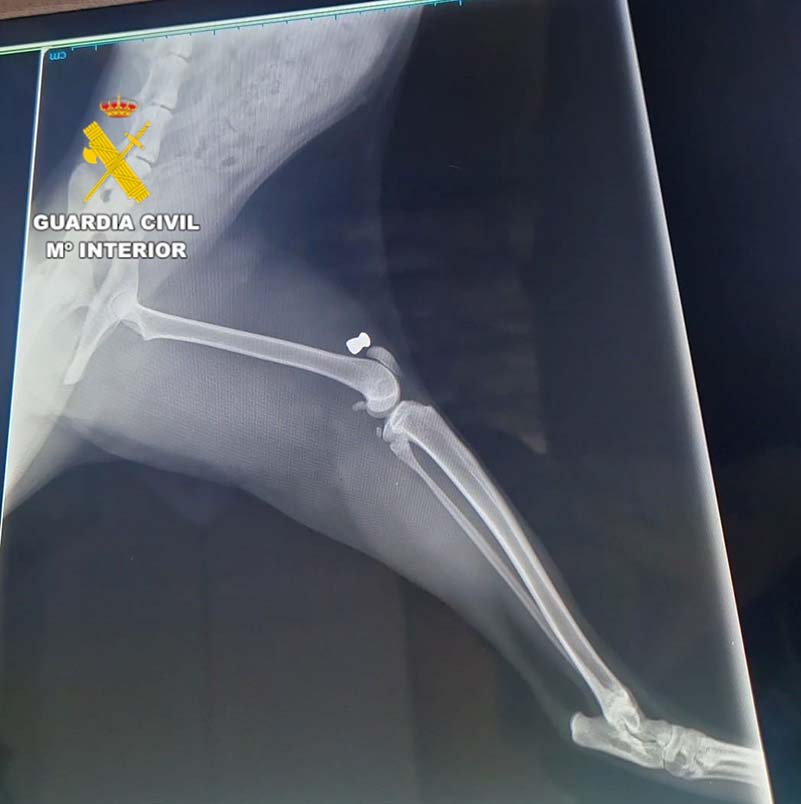

Durante el mes de septiembre, la Patrulla de SEPRONA de Segorbe inició una investigación tras ser conocedores de la muerte de tres gatos, además otros doce presentaban heridas. Durante las pesquisas obtenidas comprobaron que las lesiones eran compatibles con las producidas por impacto de perdigón de carabina de aire comprimido. Tras un examen realizado por un veterinario se confirmaron estos extremos y hallaron varios perdigones incrustados en el cuerpo de los animales.